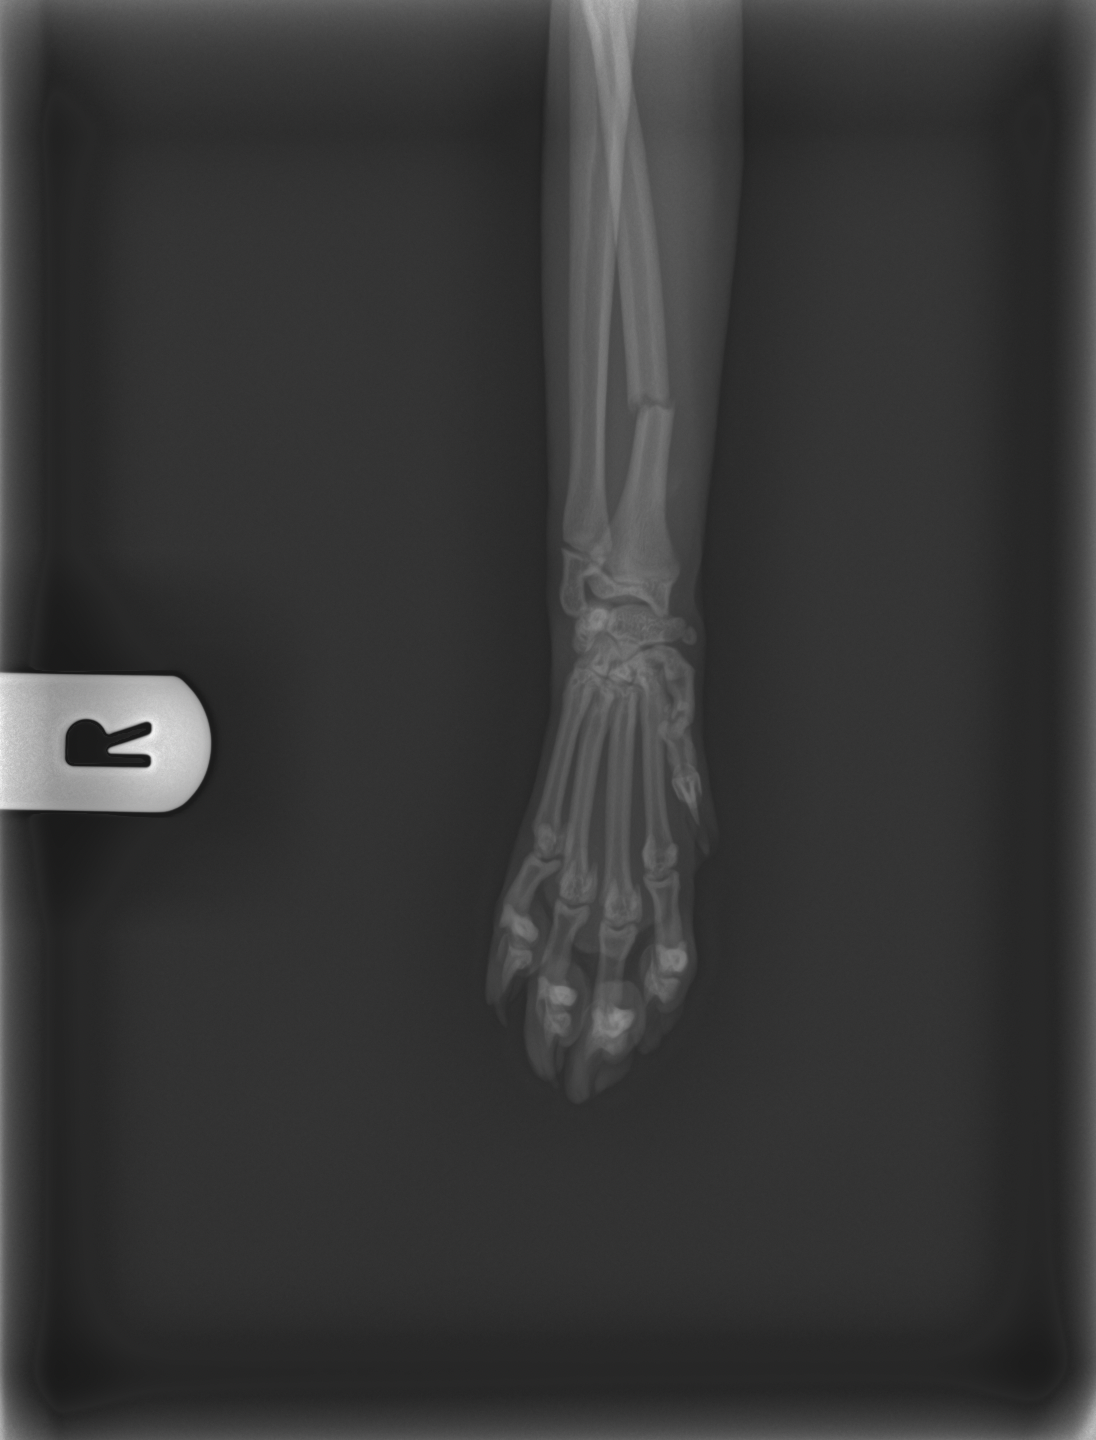

Levamo-lo de imediato ao veterinário, onde foi feita uma ecografia abdominal que, felizmente, não mostrou alterações internas. No entanto, o raio-x revelou fraturas, no rádio da pata dianteira direita e no metacarpo da pata dianteira esquerda.